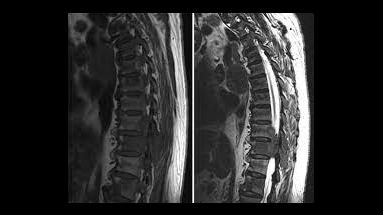

- استشاري جراحة الدماغ والأعصاب والعمود الفقري

يجمع الدكتور محمد الجلاد بين الخبرة الواسعة واستخدام التقنيات التشخيصية والجراحية الحديثة.

يتبنى الدكتور نهجًا شاملاً يضمن دقة عالية في التشخيص وفعالية متميزة في العلاج، مما يسهم في تحقيق أفضل النتائج الصحية للمرضى.